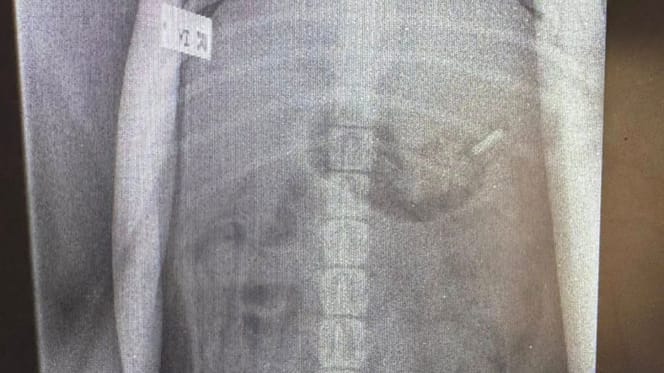

Une radio de chien

Charlie, un chiot Bull Terrier de 5 mois, s’est totalement remis après avoir avalé accidentellement une lame de rasoir trouvée dans la poubelle familiale.

© @Teme Veterinary Practice / Facebook

Les vétérinaires ont fait passer une radio à Charlie, qui a immédiatement confirmé les soupçons de ses maîtres. Alors, Charlie a été opéré en urgence. Heureusement, l'opération a été un succès et le vétérinaire a pu extraire sans difficulté la lame de rasoir du corps du toutou.